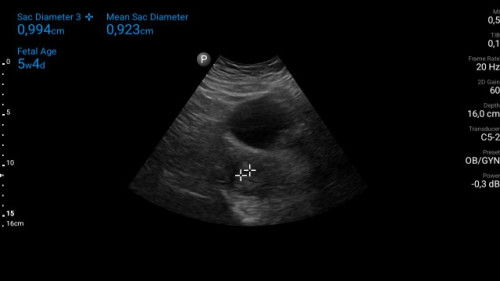

HPHT 13 feb udh telat 10 hari....tespek positif, kmrn ke dr spog utk usg....ktnya ini 5 mgg 4 hr ...

Mau tanya klo br 5 minggu emg blm terlihat janinnya ?

sama kak aku juga blm keliatan, cuma keliatan kantong hamilnya... trus suruh balik lagi bulan depan

sama ka, HPHT ku jg 13 februari... kmren USG dan hanya kantong yg terlihat...